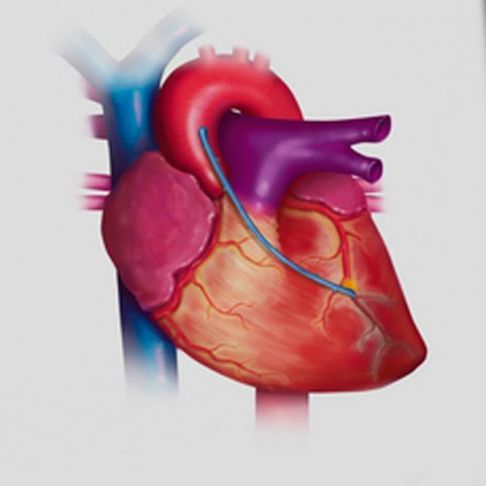

En iDoctor encontrarás: Psicólogos, Traumatólogos, Dermatólogos, Oftalmología,, Cardiología, Cirugía Maxilofacial, Cirugía general, Neurocirugía, Ginecología y Obstetricia entre otros profesionales a un solo clic y desde la comodidad de tu hogar ¡sin esperas!